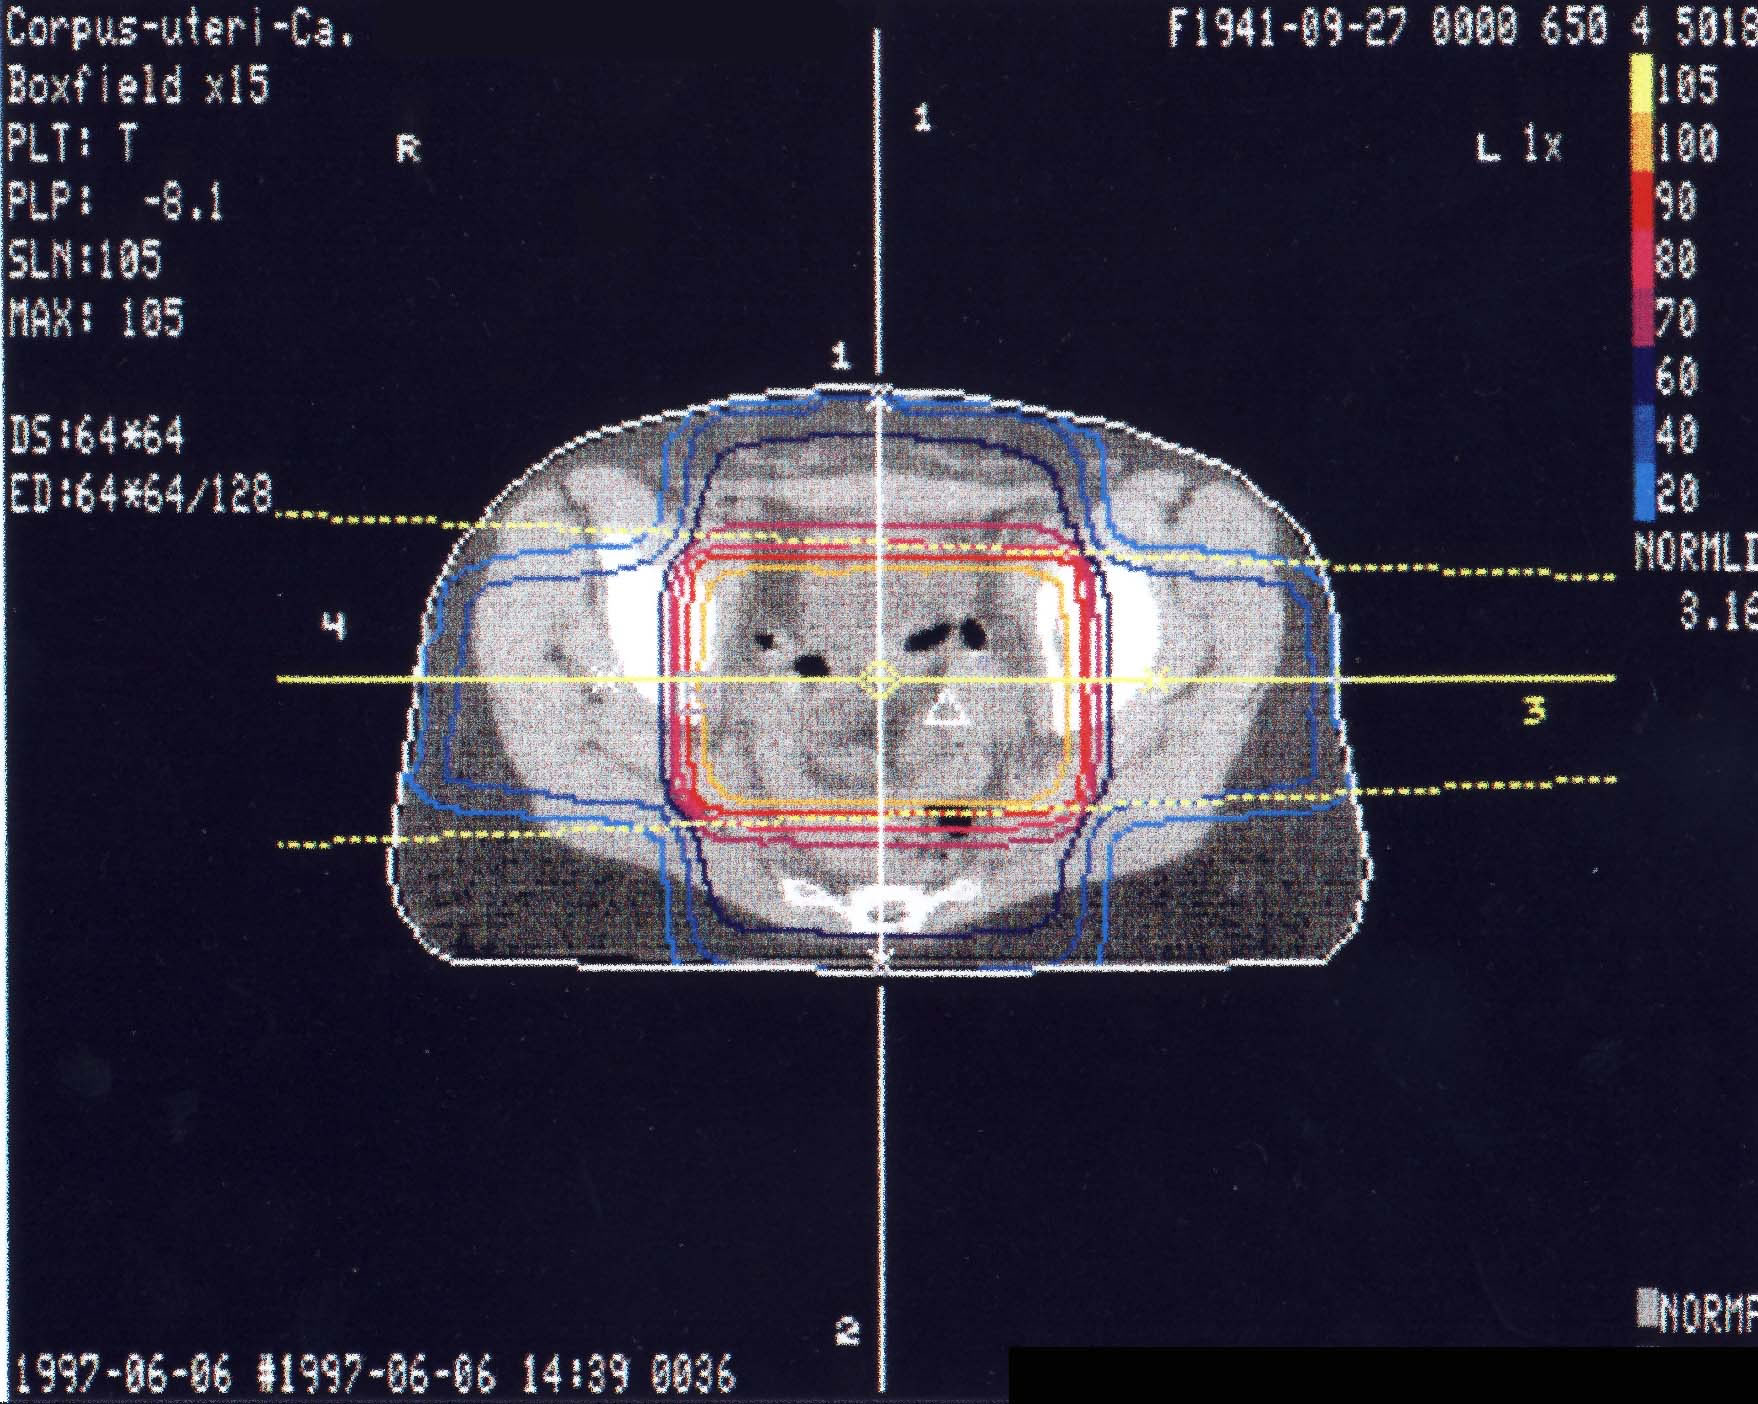

Gynäkologische Tumore des Beckens: Bestrahlungsplan

Einführung aktuelle Bilder - Einführung Bestrahlungspläne - Einführung Demonstration